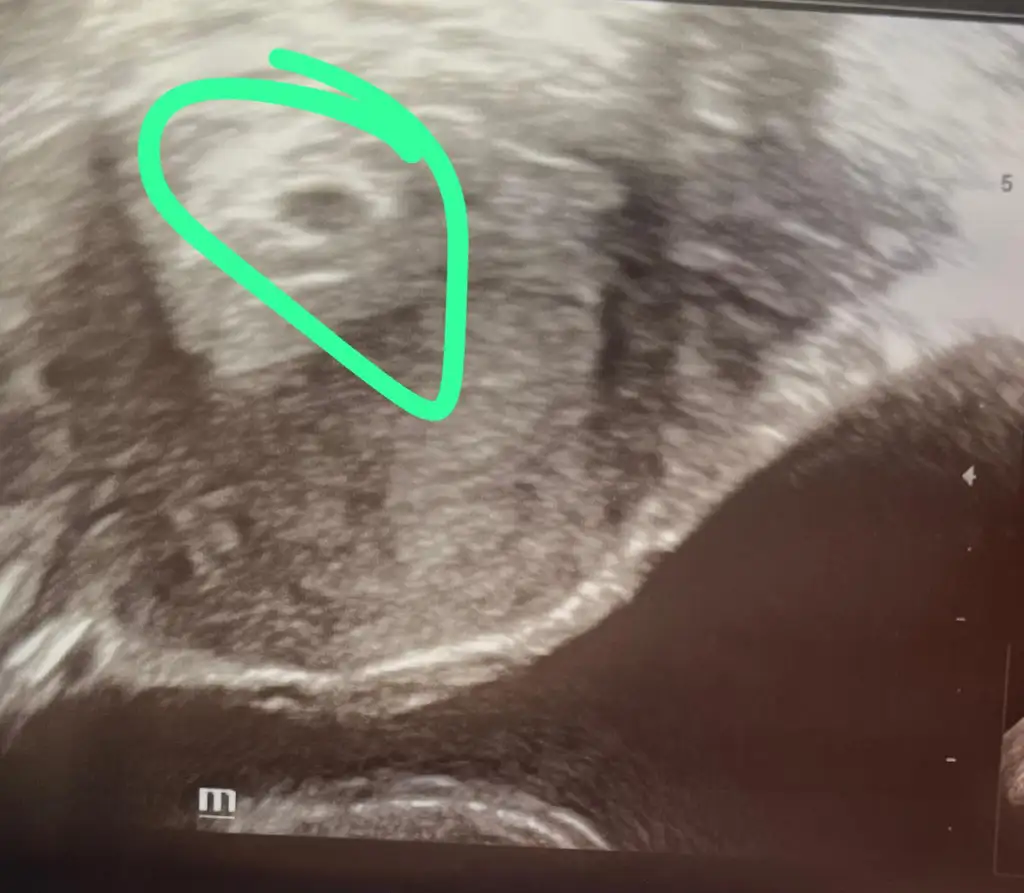

bugün doktor kontrolüne gittim uygulamaya göre 5+4 görünüyordu ama doktor çok küçük olduğunu muhtemelen geç döllenme olduğunu söyledi,

kese 2.4 mm göründü normal ultrasonla tam göremediği için vajinal baktı ve 4 haftalık baz alalım dedi bu durumda uygulama 1 hafta büyük gösteriyor.

bu durum normal mi? haftaya geri çağırdı net bakalım dedi dış gebelik yok dedi bebek şimdi ne kadarlık? bu durumda ben haziran annesi mi olacağım :D

Beni muayne eden doktor iki kese var demişti sizinde iki kese görünüyor sanırım.tek yumurta ikizi tek kesede oluyor diye biliyorum

İlk ölçümde 5 mm di sonraki hafta 6 hafta ile uyumlu ikisi de dedi. Tek yumurtadan iki ayrı kese de olabiliyormuş. Çok değişik terimleri var aynı kesede olduklarında zaten riskli oluyormuş. Ana çoğul gebelik zaten perinatolojinin gözetimi altında olması gereken bir gebelikmiş